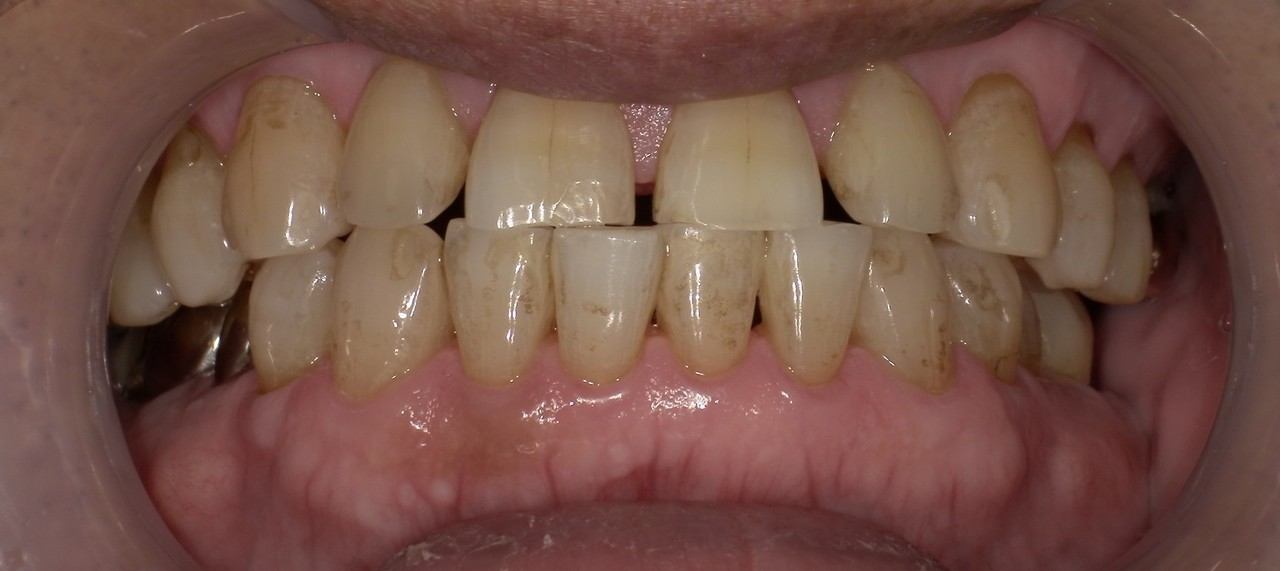

ステイン除去

BEFORE

AFTER

年齢:70代男性

治療内容:エアーフローによる歯の着色汚れ、ステイン除去

治療期間/通院回数:1回

費用: ステインコース 8,800円

リスク・副作用

①効果には個人差があり、着色汚れによっては一度に取りきれない場合があります。

施術後数時間以内に、着色効果の強いもの(コーヒー・紅茶・喫煙など)を摂取すると、歯に色素沈着が起こる可能性があります。

パウダーの刺激により歯ぐきから出血する可能性があります(痛みはほとんどありません)。